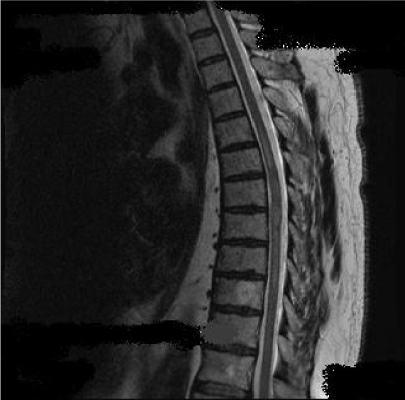

Initial brain CT scan and routine blood tests showed no abnormalities. Cervical and thoracic MRI scan revealed an intramedullary lesion extended from T1-T6, with high signal on T2 sequences (Figure1). Additionally in T3-T4 segments the lesion showed homogenous gadolinium enhancement on T1 Gd+ sequences (Figure 2a) and spinal swelling (Figure 2b). Brain MRI was normal. Due to the extensive length of the lesion a thorough investigation was performed. Immunological tests (ANA, ENA, anti-dsDNA, anti-Ro, anti-La, RF), serum B12, copper, ACE and anti-aquaporin 4 antibodies were reported negative. His cerebrospinal fluid (CSF) examination was normal (0 cells/μL, Glu: 69 mg/dL, TP: 40, 8 mg/dL) and no infective causes for the lesion were identified. The patient received intravenus methylprednisolone (1g/day) for five days but instead of clinical improvement the patient continued to deteriorate.

Figure 1: Intramedullary high signal lesion on T2 sequence extended from T1 to T6 vertebral segment.